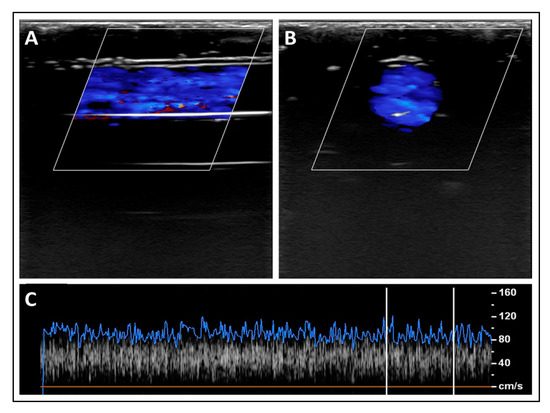

3.2. Experimental Validation of the Proposed Nanotechnology-Based Drug-Delivery System